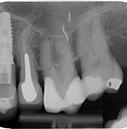

8. ábra: A műtét előtti röntgenfelvétel a 45-ös és 46-os fogat érintő súlyos szuvasodási folyamatokat mutatja.

ábra: A kezelési terület izolálása érdekében kofferdám került felhelyezésre. A szuvas foganyag eltávolítását követően körkörös matricákat helyeztünk fel az endodonciai csonkfelépítés érdekében. – 10. ábra: A hiányzó falak kiépítése. – 11. ábra: A 45-ös és 46-os fog előkészítve és megtisztítva, készen állnak a gyökércsatorna-rendszer betömésére.

kutatunk [6]. A fenti faktorok mind hatással vannak a fog várható prognózisára. Az üreg teljes körű megtisztítása lehetővé teszi, hogy szükség esetén szabályszerűen el tudjuk végezni az endodonciai csonkfelépítést, amely a későbbiekben a kofferdámizolálás felhelyezhetőségét biztosítja. Amenynyiben lehetőségünk van rá, akkor minden esetben törekedjünk végleges endodonciai csonkfelépítés készítésére. Ez jelentős mértékben megkönnyíti az endodonciai kezelések kivitelezését és hozzájárul a gyökércsatornarendszer fertőtlenítésének szakszerű kivitelezéséhez. Az endodonciai csonkfelépítés elvégzésére fordított idő többszörösen megtérül a fog – gyökértömés elkészítését követően végzett – végleges felépítése során, mivel ekkor már gyakorlatilag egy minden oldalról ép falakkal körülvett üreg feltöltését kell csak elvégeznünk (8–12. ábrák).

ábra: A jobb alsó kvadráns helyreállítása után készült röntgenfelvétel.